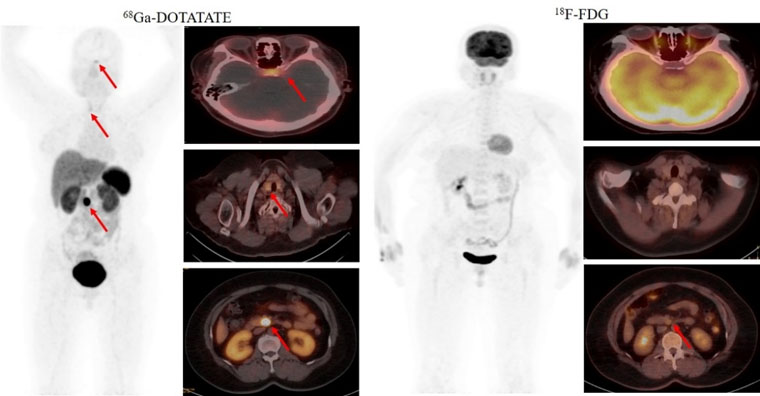

首个病例患者为一名49岁的女性,间断低血糖超过1年,甲状旁腺激素检查异常升高。脑MRI提示为脑垂体微腺瘤,上腹部MRI检查未发现明显异常。但临床怀疑胰腺存在病变,经新探针68Ga-DOTATATE PET/CT检查,发现了胰腺病灶,综合诊断多发性内分泌瘤病I型(MEN1型)。经胰腺穿刺病理证实为神经内分泌肿瘤G2。68Ga-DOTATATE及18F-FDG PET/CT双核素的检查结果为患者临床精准诊疗提供了胰腺病灶的影像学证据。

2021年5月,我院核医学科率先获得河北省最高级别的IV类放射性药品使用证书。在学科带头人赵新明教授的带领下,科室成员汲取全国优秀核医学科经验,成功开展了多种新型分子探针PET/CT临床显像工作。这些新型分子影像探针包括68Ga-DOTATATE(68Ga-生长抑素受体激动剂,针对神经内分泌肿瘤)、68Ga-JR11(68Ga-生长抑素受体拮抗剂,针对神经内分泌肿瘤)、68Ga-FAPI(68Ga-成纤维细胞活化蛋白抑制剂,针对肿瘤微环境中肿瘤相关成纤维细胞,用于各种肿瘤显像)和68Ga-PSMA(68Ga-前列腺特异性膜抗原,针对前列腺癌等多种恶性肿瘤)等,新型PET分子探针(显像剂)的应用对相关肿瘤诊断、分期和疗效评价产生了质的飞跃。